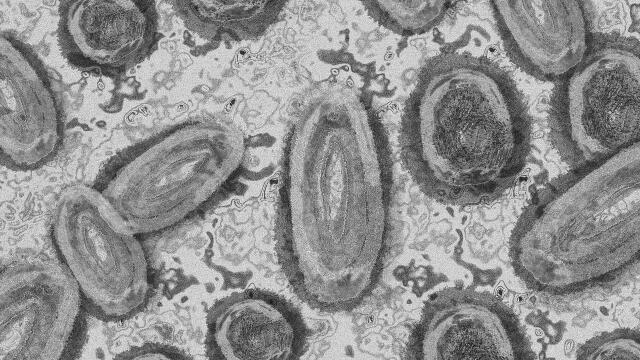

Los casos confirmados de viruela del mono en Colombia crecieron más del doble en una semana, según informó el Instituto Nacional de Salud y el Ministerio de Salud.

Los casos llegan a 582, siendo Bogotá la ciudad con más reportes: 442. Otros 62 contagios se confirmaron en Antioquia, 18 en Cundinamarca, 14 en Cali, 10 en Tolima y el restante en 16 departamentos.

Según las autoridades de salud, en 42,6% de los casos se desconoce la fuente de contagio de viruela del mono en Colombia y el 15,8% están relacionados con esas fuentes desconocidas. Solo un 4,3% de los casos se clasifican como importados.